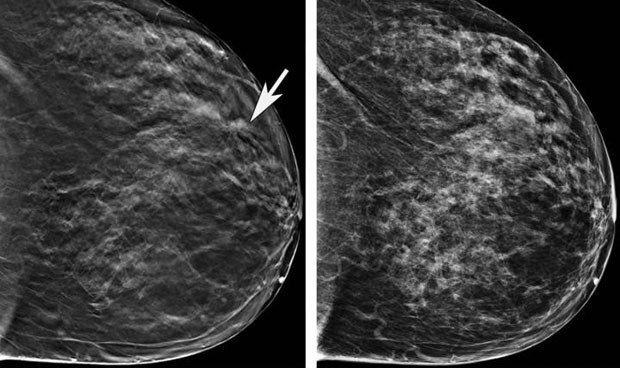

En la carrera por detectar la enfermedad lo antes posible, las nuevas tecnologías y la inteligencia artificial están jugando un papel fundamental para detectar más cáncer y más pequeños siendo una herramienta de ayuda para el radiólogo, que no solo es más eficaz en su diagnóstico, sino que puede gestionar mejor las cargas de trabajo.

Para facilitar un cribado más efectivo, tras la revisión de las nuevas evidencias científicas, y ayudados por las nuevas tecnologías aplicadas al cribado como la tomo síntesis y la inteligencia artificial, la UE aconseja bajar la edad de cribado a 45 años y concluir a los 75 en mujeres asintomáticas con riesgo intermedio.